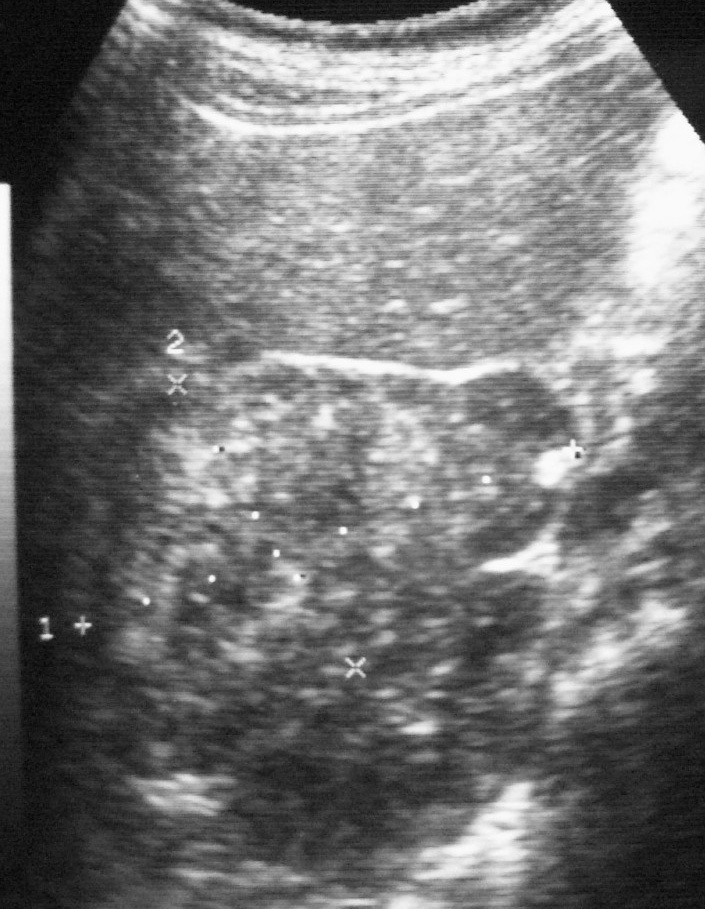

El tumor rabdoide se presentó en un niño de 5 meses estudiado por masa abdominal palpable y hematuria, con el antecedente de un hermano gemelo fallecido poco tiempo antes por tumor cerebral. El estudio con ecografía y TC abdominal demostró una masa renal sólida, heterogénea e hipodensa con poco realce. Se completó el estudio con ecografía transfontanelar y TC craneal identificando una masa cerebral sincrónica, intraaxial, frontal paramedial, sólido-quística con calcificaciones (fig. 7). No se conoció la histología del tumor cerebral por seguimiento del paciente en otro centro.

Fig. 7 Tumor rabdoide. Niño de 5 meses con hematuria y masa abdominal. (A) Ecografía abdominal. Corte longitudinal renal izquierdo. Masa sólida, heterogénea (M), bien delimitada en polo inferior de riñón izquierdo. (B) Tomografía computarizada abdominal con contraste intravenoso. Masa renal hipodensa, de aspecto infiltrativo, con crecimiento extrarrenal y tenue captación de contraste. (C) Tomografía computarizada craneal. Masa intraaxial, sólido-quística, fronto-temporal derecha, que desplaza la línea media, con un área de calcificación periférica.